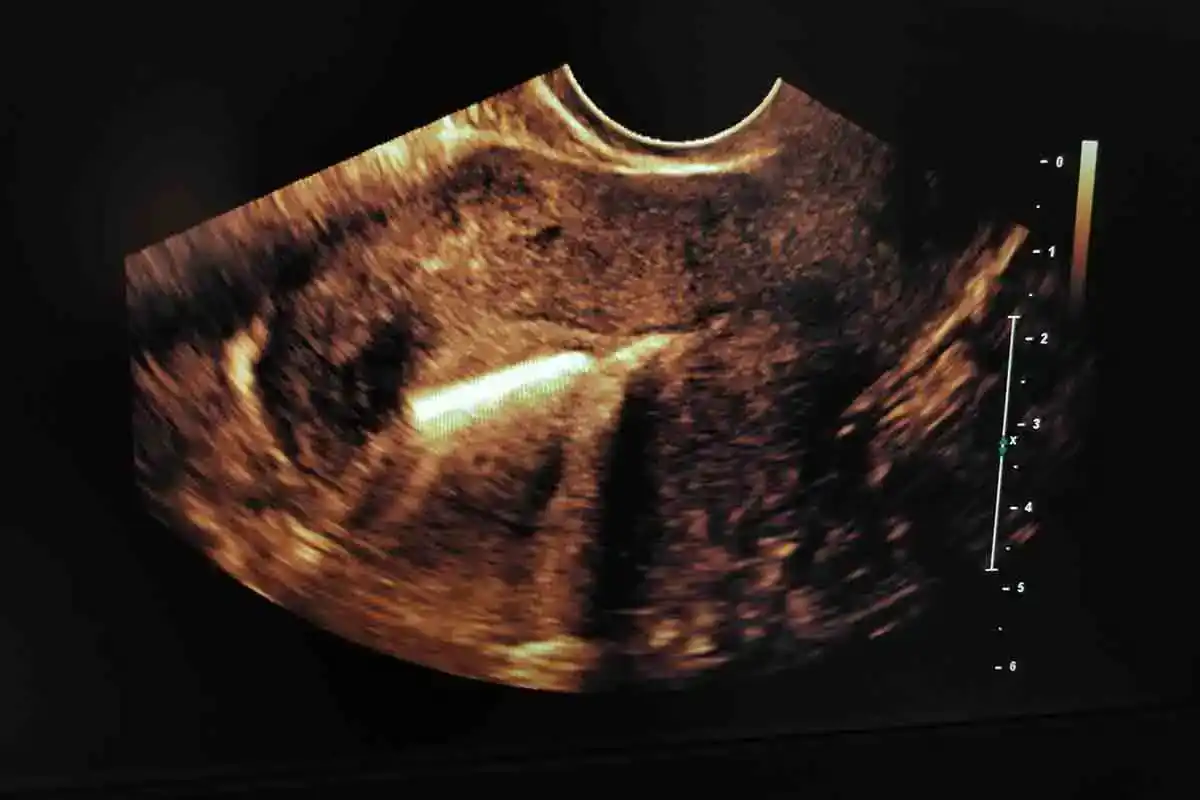

Váš lékař provede ultrazvuk a zkontroluje, zda je těhotenství životaschopné nebo mimoděložní. Pokud se potvrdí životaschopné těhotenství, IUD by mělo být odstraněno, aby se dosáhlo ideálních výsledků pro vás a vaše dítě. Neodstranění IUD může zvýšit riziko infekce (septický potrat nebo chorioamnionitida), potrat, mrtvé narození a předčasný porod. Pokud je však zařízení přemístěno na místo, které vyžaduje chirurgický zákrok, který může ovlivnit plod, může se váš lékař rozhodnout ponechat zařízení na místě.